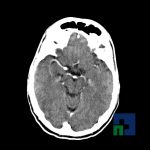

- Evaluarea deplasării liniei mediane

- Evaluarea cisternelor perimezencefalice

- Diagnosticul edemului cerebral, a contuziei cerebrale, a leziunilor axonale difuze edematoase/hemoragice, a dilacerării cerebrale, a hematomului intraparenchimatos posttraumatic, a hematoamelor subdurale/extradurale (acute, subacute, cronice), a hemoragiei intraventriculare, a hemoragiei subarahnoidiene